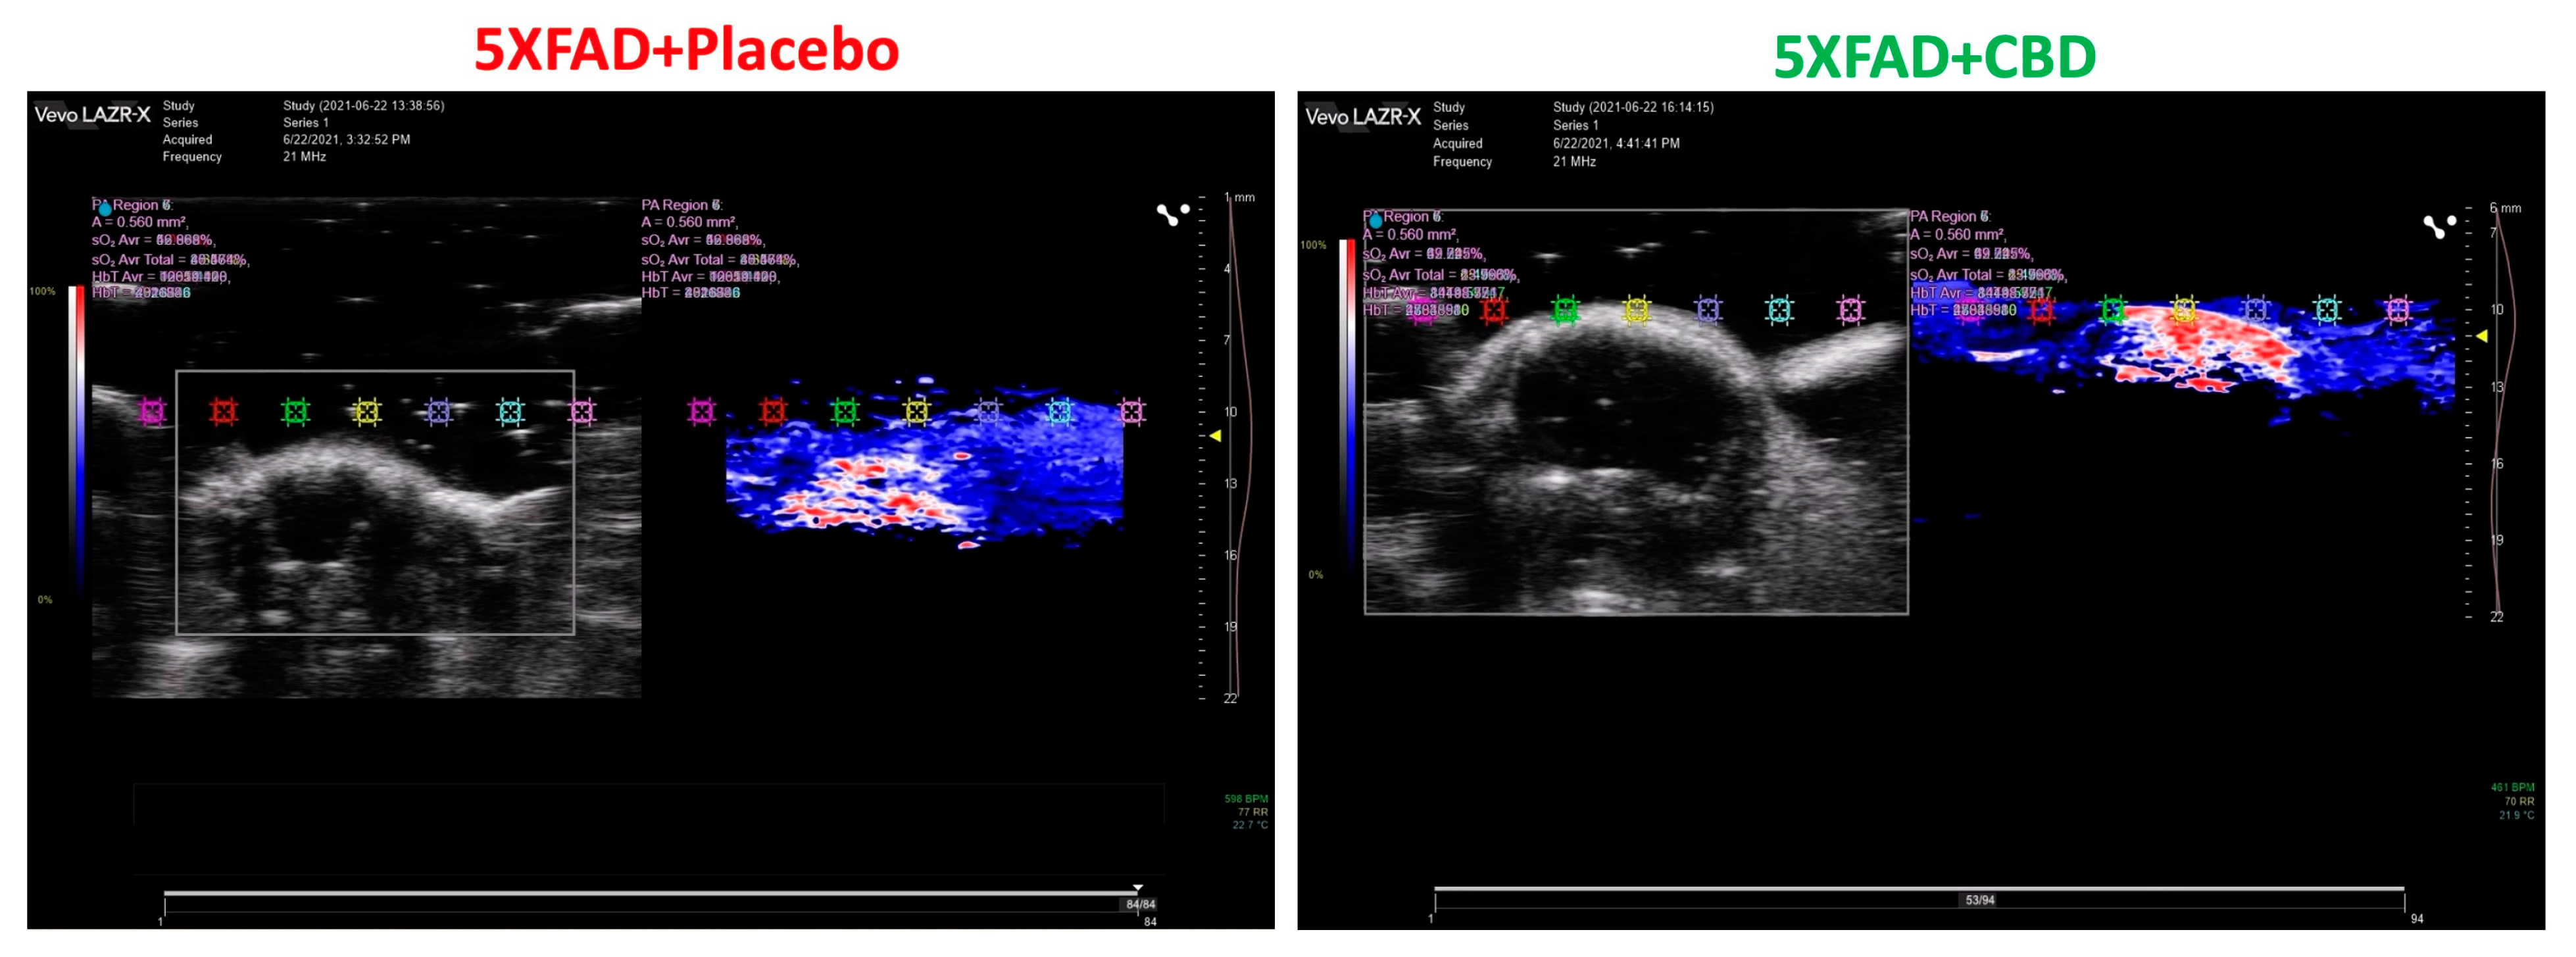

2.2. Inhalant CBD Improved Cerebral Blood Flow in AD

4.3. Photoacoustic Imaging of Brain